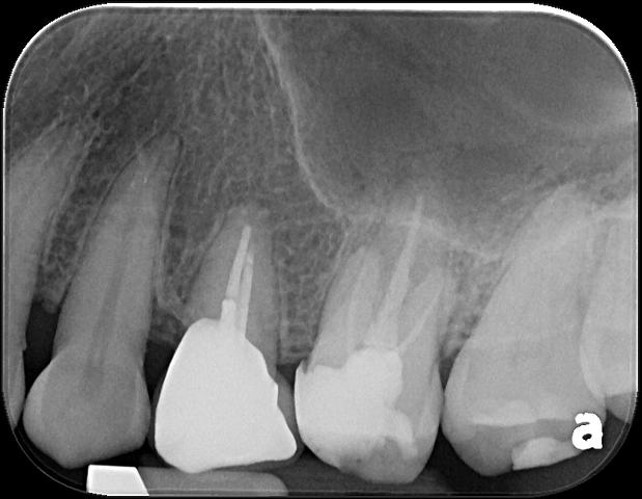

治療前,右上第二小臼齒疼痛

治療前,第二小臼齒根尖病變